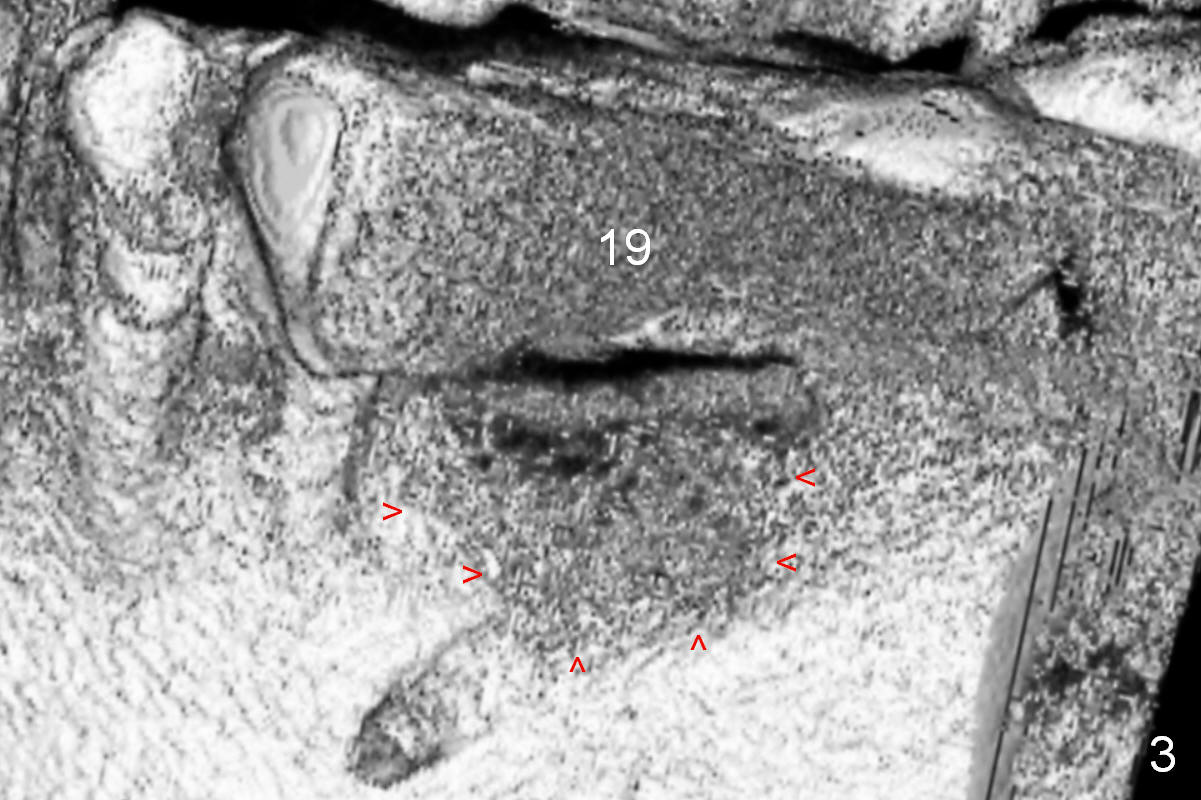

A 68-year-old lady has had a lower right bridge for 10 years (Fig.1,2 (CBCT section), Fig.3 (3 D image)).  There is caries underneath #20 retainer (mesiolingual) with symptom.  The retainer and the pontic at #19 will be removed.  The tooth #20 may need root canal therapy.  An implant will be placed at #19, but the crest is narrow (Fig.2 coronal section).

Bone density at the crest appears to be low (Fig.3 arrowheads).  After pontic removal (Fig.4 black area) and incision, use #15 scalpel, bone scalpels and bone blades to start bone expansion (red line).  Bone expansion continues with D osteotomes (Fig.5 red area) which mainly moves the buccal plate (B) buccally.  The 3rd step of bone expansion is to use RT (round tapered) osteotomes or bone expanders (Fig.6 white circle); the buccal plate keeps being expanded more the lingual one (L).  When an implant is placed, the lateral spaces created by expansion will be filled with bone graft.  If the depth of osteotomy is not enough, use drills to reach the desired one.